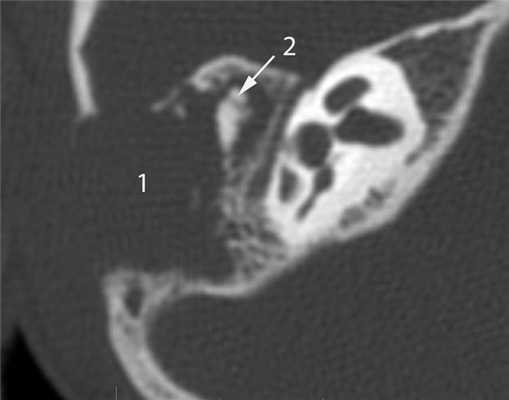

КТ-признаки злокачественной опухоли височной кости предопределяются происходящими в ней патоморфологическими изменениями. Так, наличие опухолевых масс в среднем ухе на КТ проявляется нарушением пневматизации полостей среднего уха (рис. 1). Рисунок 1. Лангергансоклеточный гистиоцитоз. Аксиальная проекция правой височной кости. Отсутствует пневматизация полостей среднего уха за счет наличия опухоли (1), вызывающей обширные деструктивные изменения в пирамиде. Цепь слуховых косточек сохранена (2). Степень выраженности данного КТ-симптома обусловлена размерами самой опухоли и ее точной локализацией в височной кости. Нарушение пневматизации полостей среднего уха не является специфичным для новообразований и постоянно встречается при других заболеваниях среднего уха, в первую очередь при остром и хроническом средних отитах.